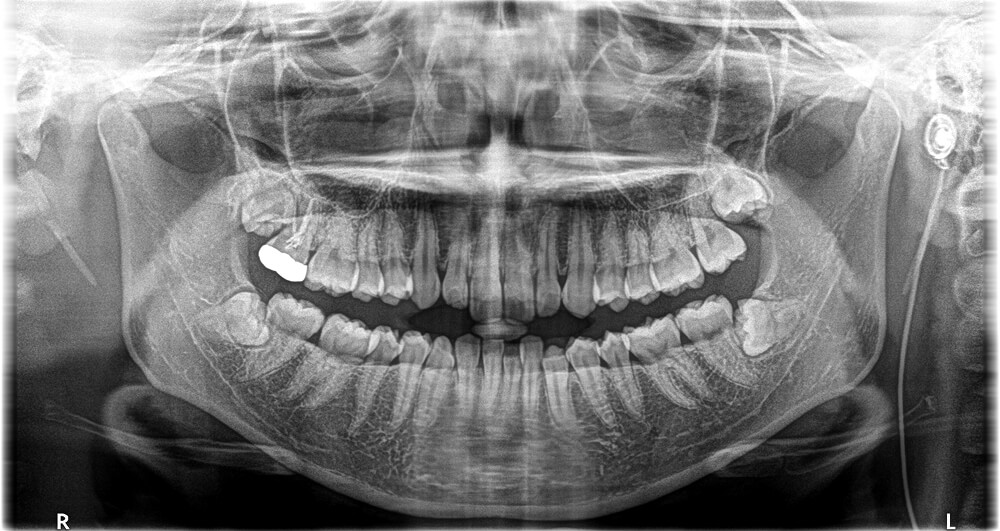

親知らずの抜歯は、見た目だけでは難しさが分からないことがあります。神経との距離や歯の向き、骨の状態を確認し、安全に進められるかを見極めます。院内で対応できる場合はそのまま治療へ進みます。より高度な管理が必要なときは、総合病院や大学病院での治療について丁寧に説明します。

歯ぐきや骨の中に埋まっている親知らず(埋伏歯)や、横向きに生えている歯も、検査のうえで院内対応が可能なケースがあります。歯ぐきを開き、必要に応じて歯を分けて取り出します。処置は局所麻酔で行います。

歯ぐきや骨の中に埋まっている(埋伏歯)場合は、歯ぐきを開き、必要に応じて歯を分けて取り出します。

※神経に近い場合や全身管理が必要なときは、総合病院や大学病院での治療をご提案します。